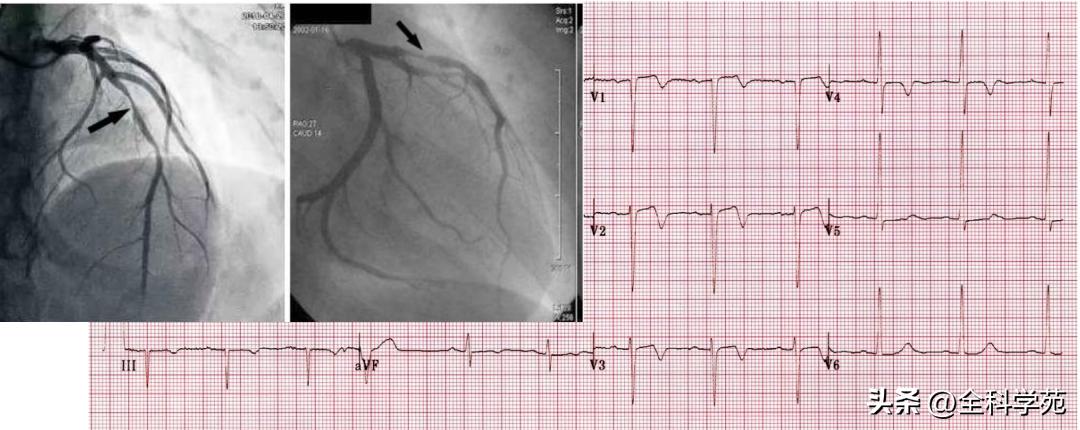

(1)不稳定心绞痛

- 37岁女性,既往有心绞痛病史,因胸骨后疼痛入急诊。

- 心电图显示V1~V5导联T波倒置,予硝酸甘油后症状缓解,心肌酶(-)

(2)Wellens综合征

1)1982年, Wellens等人提出Wellens现象,即前降支近端狭窄患者存在特征性T波改变,此后,人们将其命名为Wellens综合征,其图形有2种形态

2)1型Wellens综合征:ST位于等电位线,或呈直线型或拱形轻度抬高(<1 mm),紧接对称性倒置T波,通常见于V2~V3导联,也可见于V1~V4导联

3)2型Wellens综合征,主要为V2~V3导联,T波呈正负双相

4)胸痛缓解期T波倒置:由于冠脉存在严重病变,心外膜缺血更重→出现心肌顿抑及心肌“冬眠”,导致心外膜复极化过程变慢,复极化方向由心内膜指向心外膜,出现T波双向或倒置

5)胸痛发作时T波假性正常化:前降支暂时性完全或几乎完全闭塞导致远端心肌严重缺血,心内膜缺血更重,从而心内膜复极化过程比心外膜慢,复极化方向恢复为心外膜指向心内膜,使倒置的T波变浅或直立